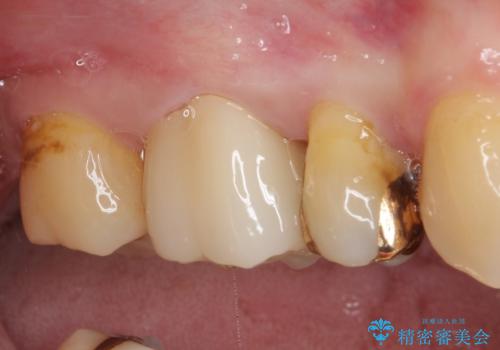

- 奥歯の裏側がしみるとのことで来院された患者様です。

矯正治療による歯肉退縮がおき、歯根にまで虫歯が波及していました。

虫歯が大きかったため、フルジルコニアクラウンにて補綴することとしました。

一部歯肉の中にまで虫歯が波及しており、汚れが溜まりやすくなっていましたが、クラウン装着後は汚れが溜まることはなくなりました。